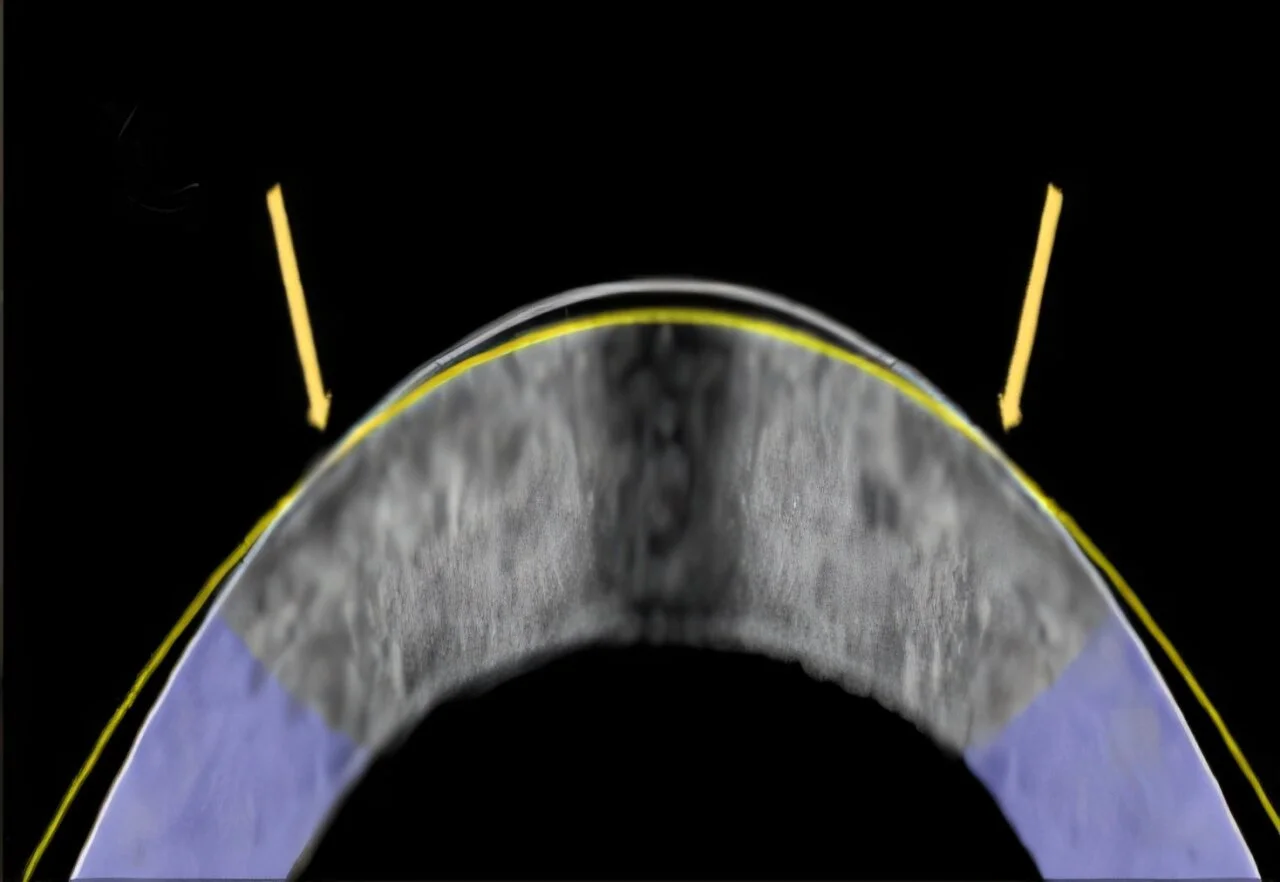

Researchers are developing an alternative to LASIK using electromechanical reshaping (EMR), a technique that reshapes the cornea without lasers or incisions, by altering tissue pH with electric potential. Early animal studies show promising results, including potential reversibility and fewer risks, but further research is needed before clinical application.